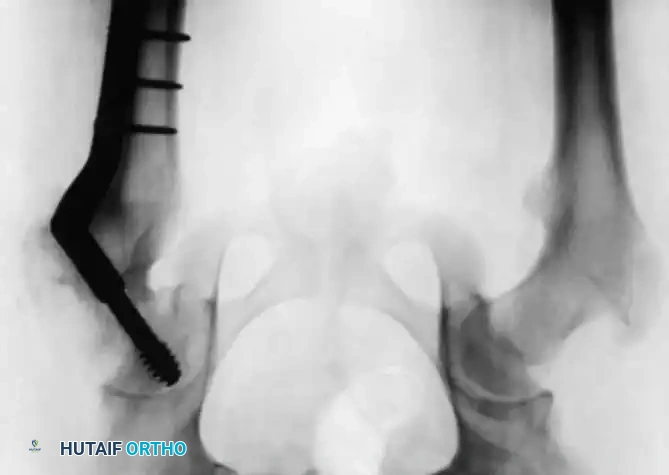

Radiographic Gallery: Diagnosis and Evaluation

Associated Surgical & Radiographic Imaging